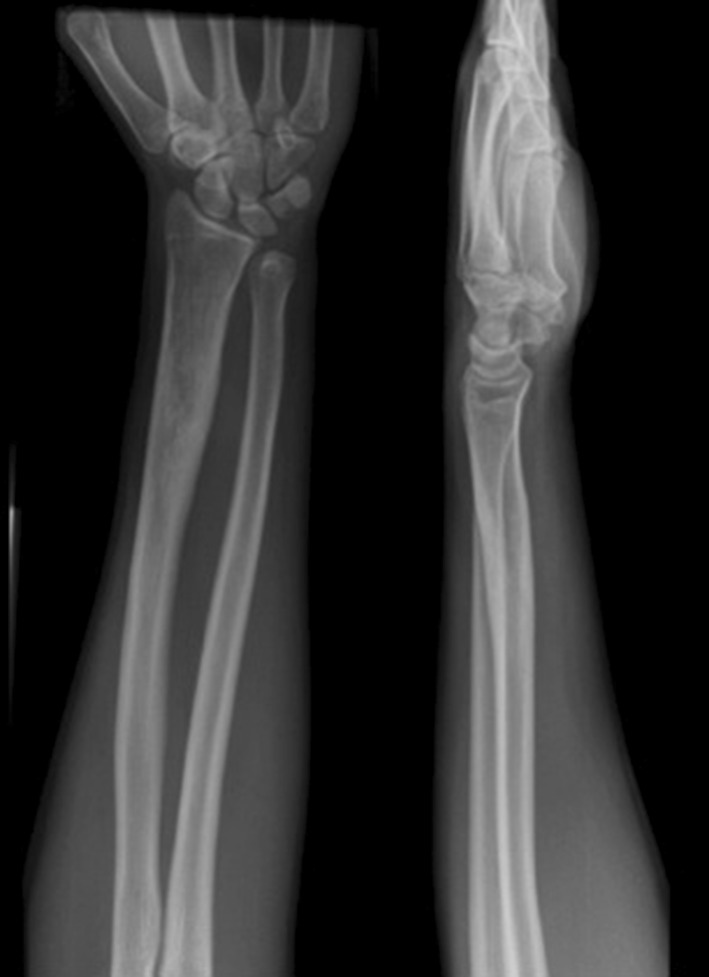

Fig. 2.

AP radiograph of the left distal radius showing an intramedullary lytic lesion